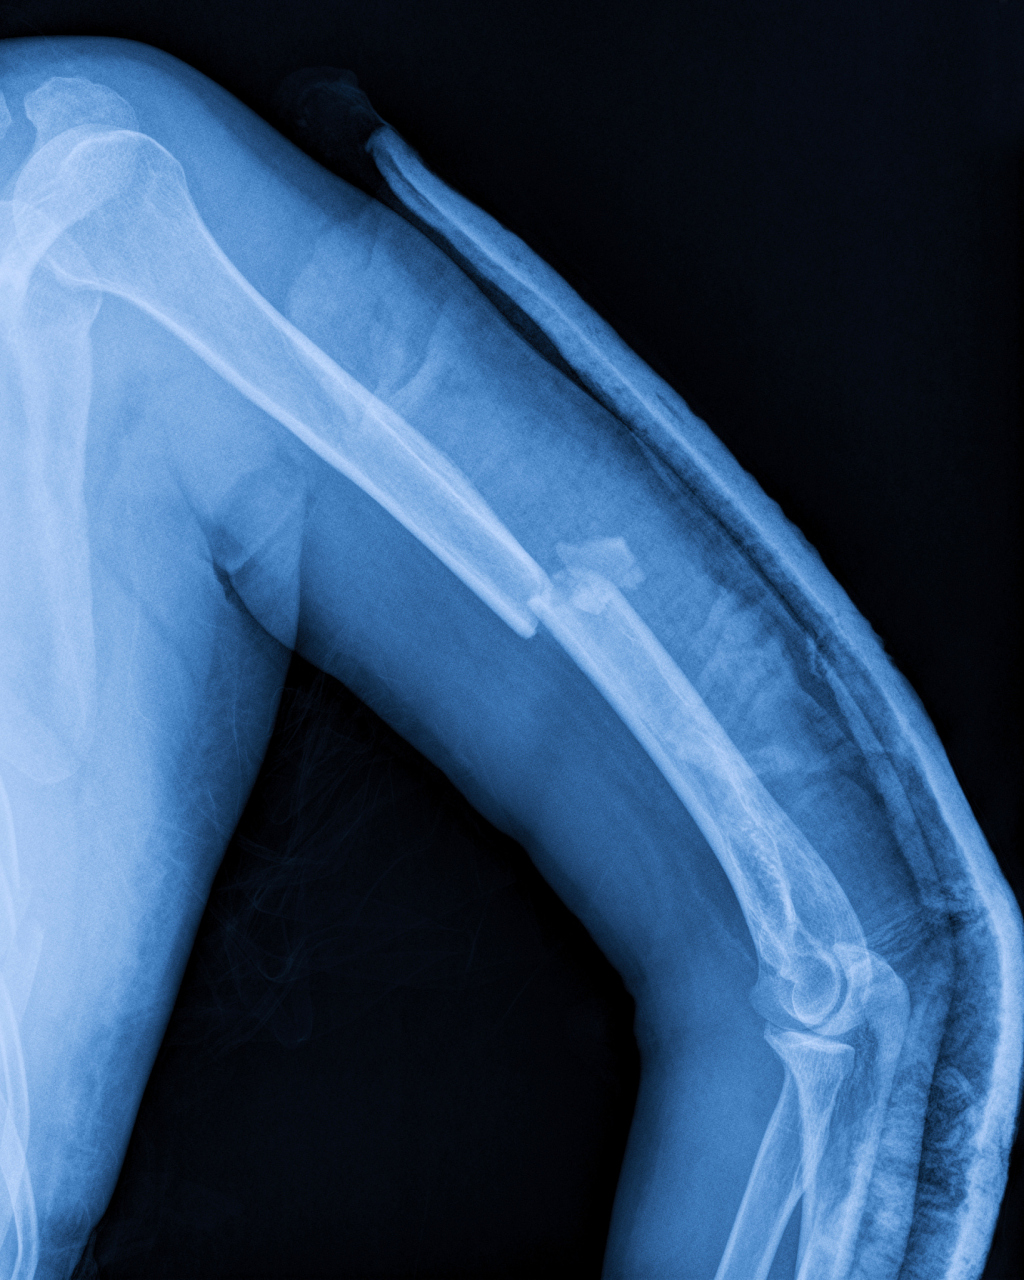

愈合细中求机器皮带绞伤开放性肱骨骨折

图片尺寸2166x3145